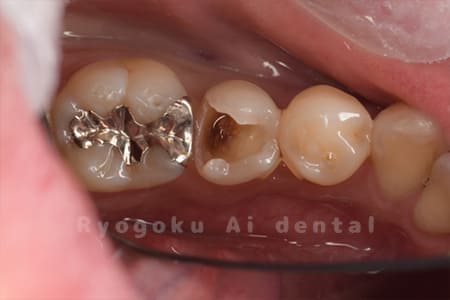

Case11

-

- 原因

- インレー2次カリエス、ならびにインレー脱離

- 治療内容

- セラミッククラウン、セラミックインレー

- 治療費用

- 123,000円×2(セラミッククラン)、77,000円(セラミックインレー)

銀歯が取れて、ご来院された患者様です。奥歯2本をセラミッククラウン、手前の小臼歯をセラミックインレーで治療を行いました。

<リスク・副作用>

過度の咬合や衝撃で割れることがあります。